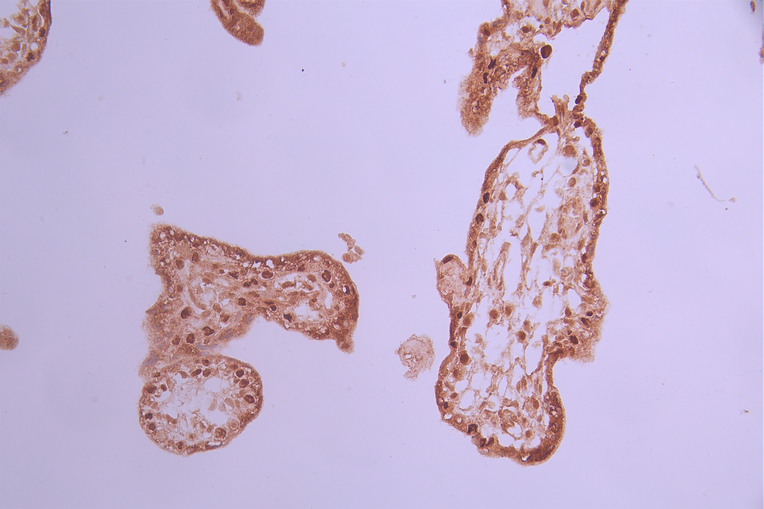

IHC image of CSB-RA586611A0HU diluted at 1:100 and staining in paraffin-embedded human placenta tissue performed on a Leica BondTM system. After dewaxing and hydration, antigen retrieval was mediated by high pressure in a citrate buffer (pH 6.0). Section was blocked with 10% normal goat serum 30min at RT. Then primary antibody (1% BSA) was incubated at 4°C overnight. The primary is detected by a Goat anti-rabbit polymer IgG labeled by HRP and visualized using 0.05% DAB.